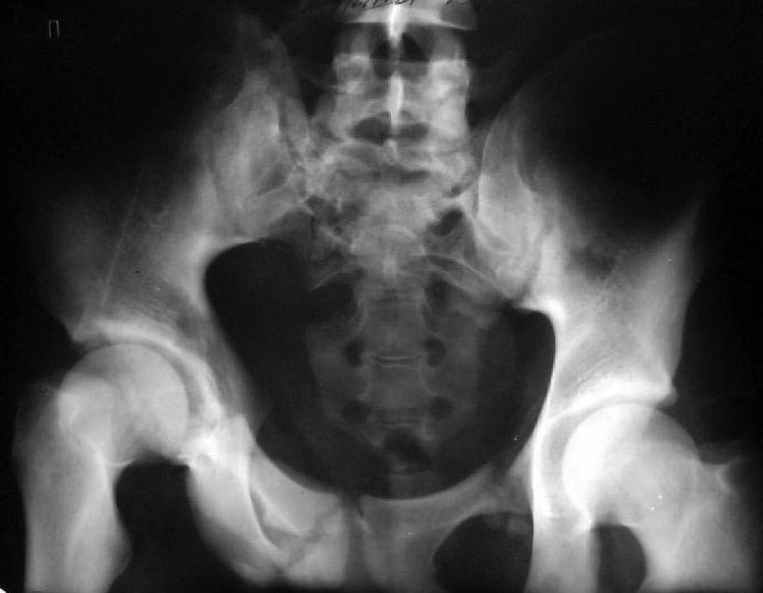

Уважаемый Юрий Алексеевич, обсудить показания к оперативному лечению возможно после выяснения полной клинической картины (боль, опороспособность, ходьба, сидение, половая функция, неврологический статус), данные кт и косых проекций.

Для информации к размышлению о возможности исправления имеющейся деформации предлагаю похожий случай.